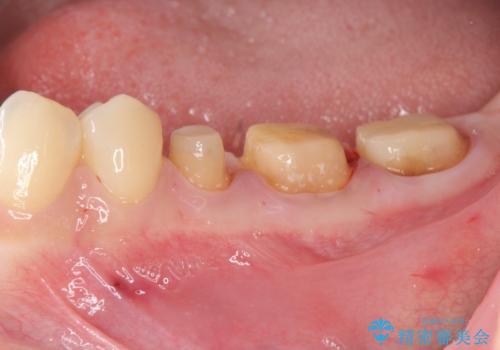

深い虫歯 歯周外科を併用した精度の高い補綴治療

- 治療途中で放置してしまった歯の治療の再開を希望され来院されました。

虫歯を除去すると、歯ぐきよりも深い虫歯であることが判明したため歯周外科を行い問題を解決していきます。